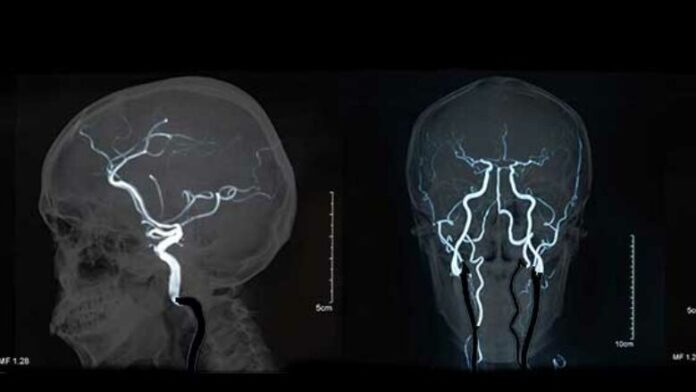

Me zhvillimin e procedurave moderne diagnostikuese, kryesisht skanerëve dhe imazherisë me rezonancë magnetike, procedurave angiografike dhe disponueshmërisë së tyre më të madhe, numri i pacientëve te të cilët aneurizma zbulohet “në kohë” para se të shpërthejë, është duke u rritur.

Pasi aneurizma zbulohet me anë të këtyre metodave, karakteristikat e saj morfologjike analizohen për të vlerësuar rrezikun e rupturës. Rreziku i rupturës së saj është më i madh me aneurizmat më të mëdha se pesë milimetra.

Aneurizmat e vendosura në bifurkacionet e enëve të mëdha të gjakut në tru, veçanërisht arteria cerebrale e mesme, arteria komunikuese anteriore dhe arteria bazilare, shoqëroheshin më shpesh me një rrezik më të lartë të këputjes. Madje, dhe aneurizmat e parupturuara mund të shkaktojnë simptoma të caktuara.